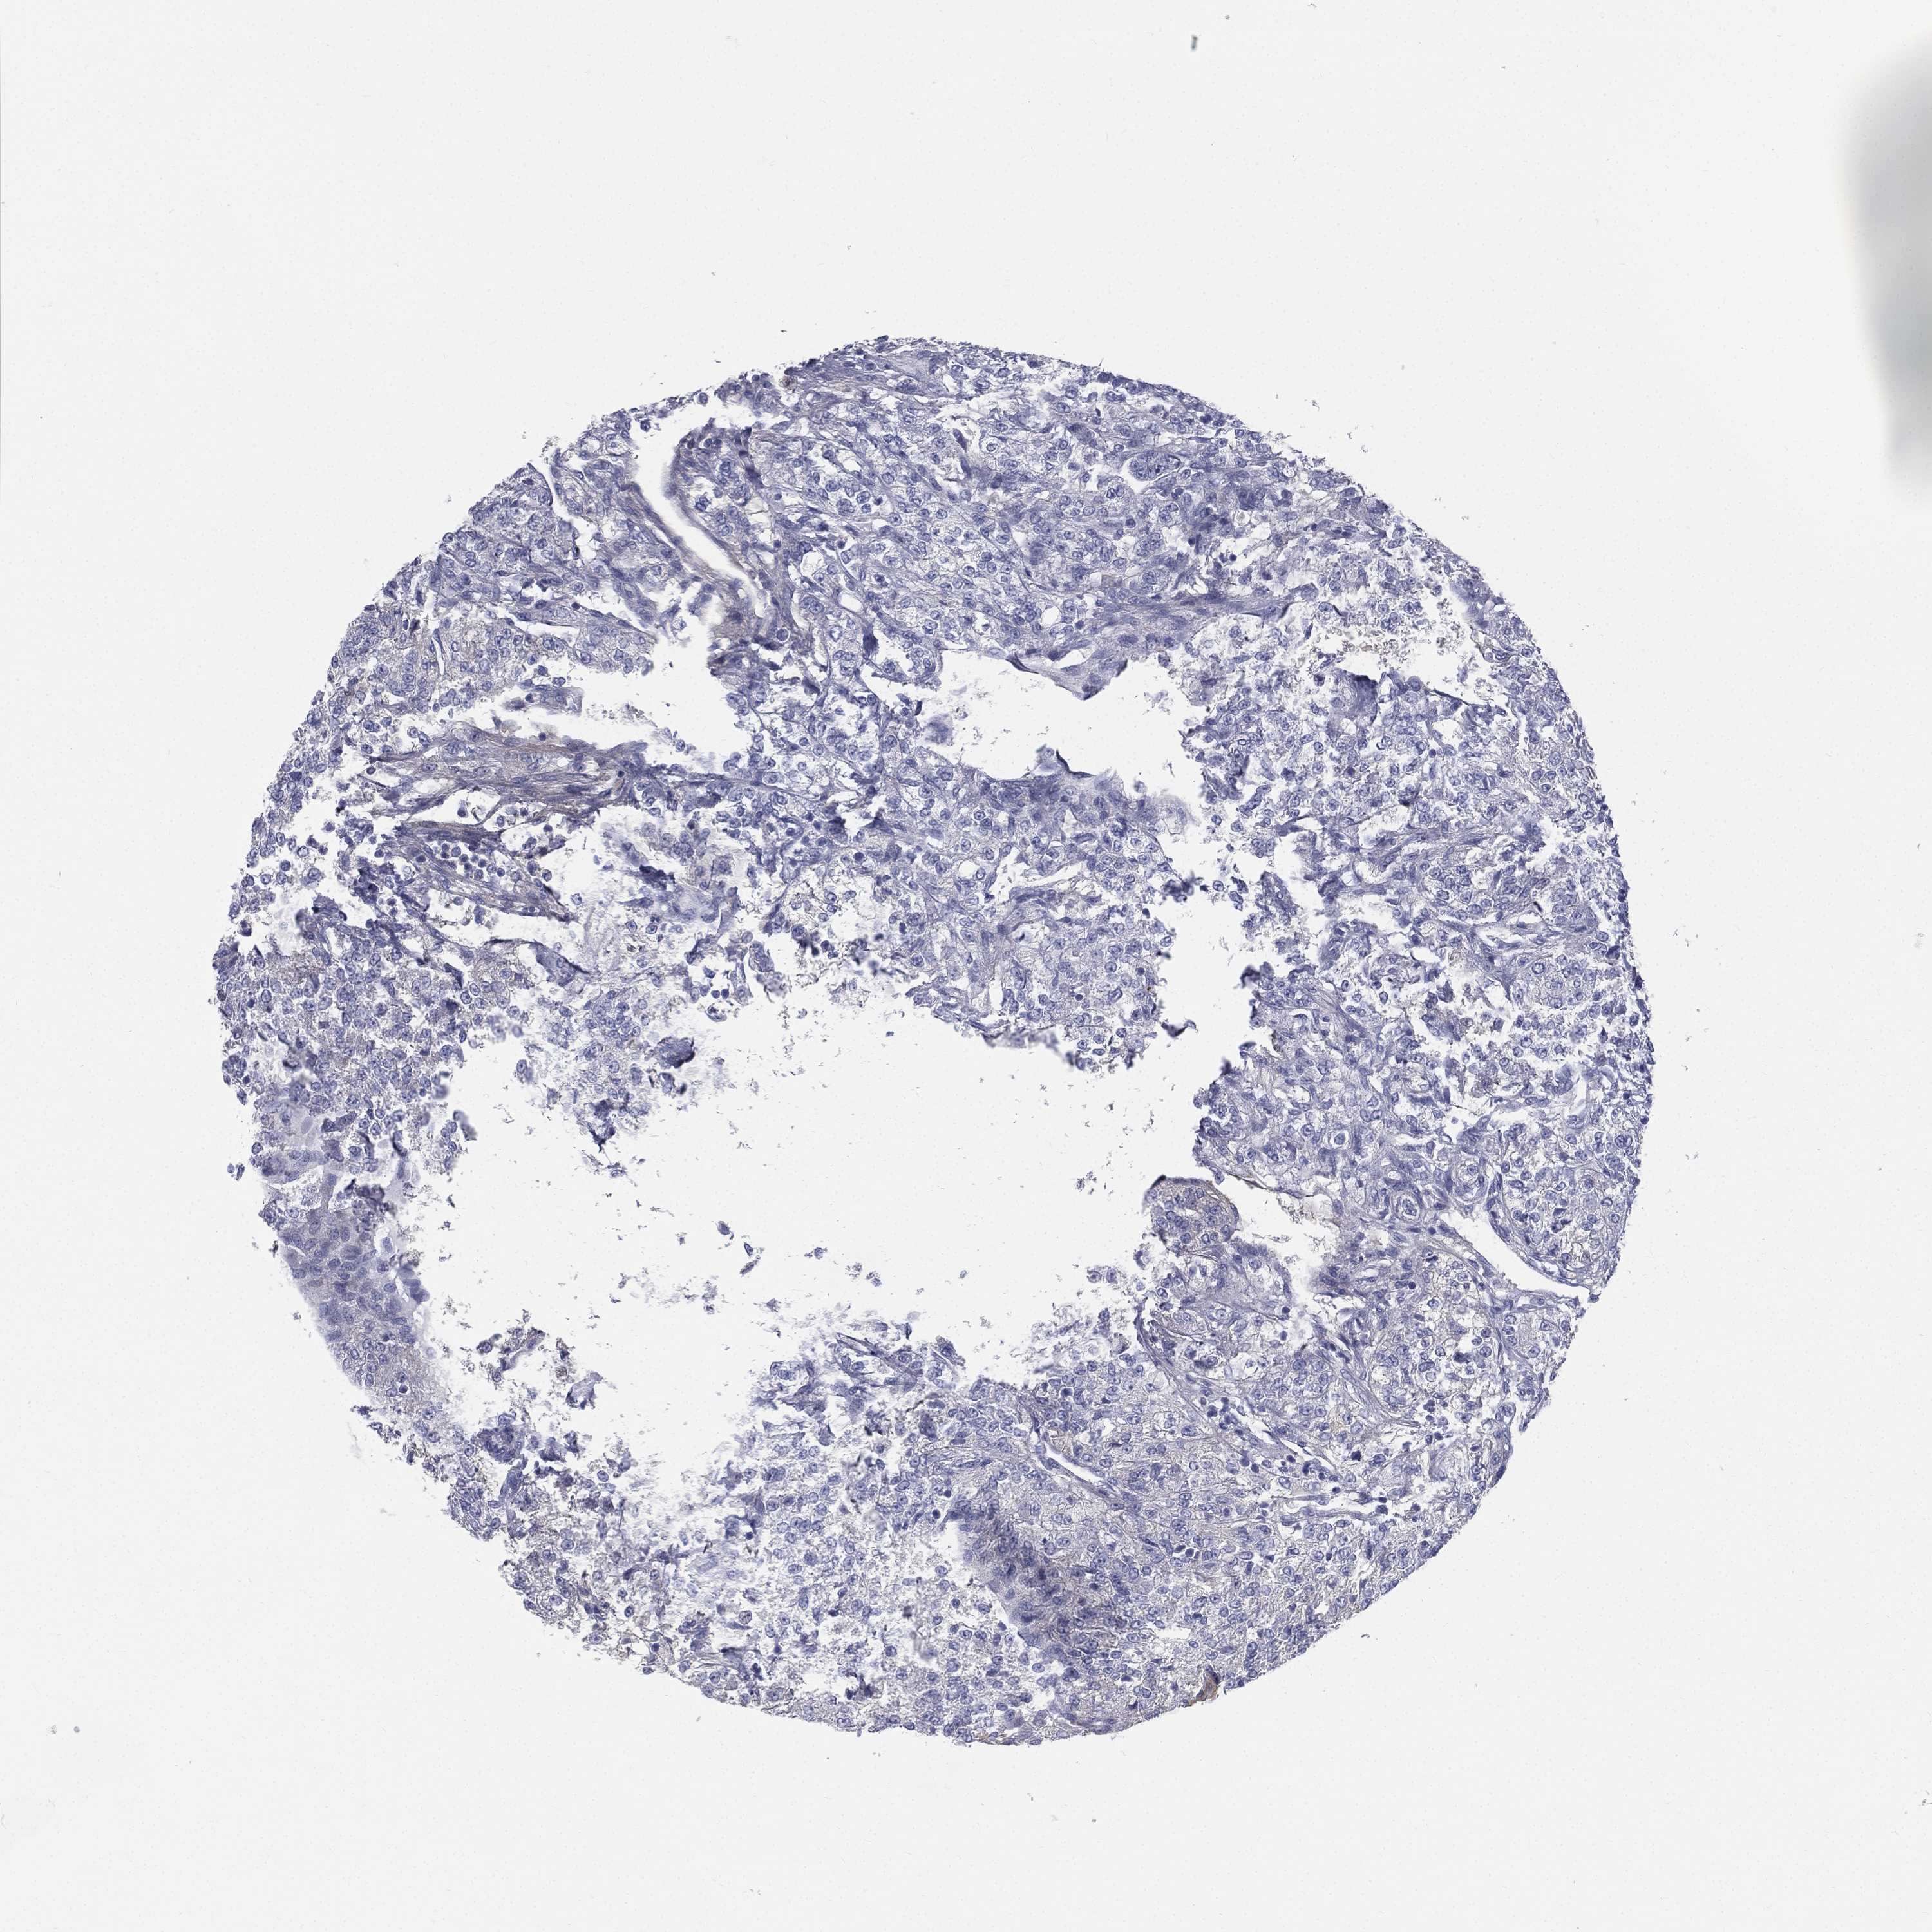

KIDNEY RENAL CLEAR CELL CARCINOMA (TCGA) - Interactive survival scatter ploti

The Survival Scatter plot shows the clinical status (i.e. dead or alive) for all individuals in the patient cohort, based on the same data that underlies the corresponding Kaplan-Meier plots. Patients that are alive at last time for follow-up are shown in blue and patients who have died during the study are shown in red.

The x-axis shows the expression levels (FPKM) of the investigated gene in the tumor tissue at the time of diagnosis. The y-axis shows the follow-up time after diagnosis (years). Both axes are complimented with kernel density curves demonstrating the data density over the axes. The top density plot shows the expression levels (FPKM) distribution among dead (red) and alive patients (blue). The right density plot shows the data density of the survived years of dead patients with high and low expression levels respectively, stratified using the cutoff indicated by the vertical dashed line through the Survival Scatter plot. This cutoff is automatically defined based on the FPKM cutoff that minimizes the p-score. The cutoff can be changed by dragging the vertical line or by entering a cutoff value in the square labeled "Current cut-off".

Under the Survival Scatter plot the p-score landscape (black curve; left axis) is shown together with dead median separation (red curve; right axis). Dead median separation is the difference in median mRNA expression between patients who have died with high and low expression, respectively. It is calculated as follows: median FPKM expression of dead patients with high expression - median FPKM expression of dead patients with low expression. This is intended to aid the user in visually exploring custom cutoffs and the associated p-scores and dead median separation.

Individual patient data is displayed and can be filtered by clicking on one or more of the category buttons on the top of the page. Categories describing expression level and patient information include: high, low, alive, dead, female, male and tumor stages. The scale of the x-axis can be toggled between linear and log-scale by clicking on the "x log" button. Mouse-over function shows TCGA ID, patient information and mRNA expression (FPKM) for each patient.

& Survival analysisi

Kaplan-Meier plots summarize results from analysis of correlation between mRNA expression level and patient survival. Patients were divided based on level of expression into one of the two groups "low" (under cut off) or "high" (over cut off). X-axis shows time for survival (years) and y-axis shows the probability of survival, where 1.0 corresponds to 100 percent.

HP is validated prognostic, high expression is unfavorable in Kidney Renal Clear Cell Carcinoma (TCGA)

Best expression cut offi

Based on the FPKM value of each gene, patients were classified into two groups and association between prognosis (survival) and gene expression (FPKM) was examined. The best expression cut-off refers the FPKM value that yields maximal difference with regard to survival between the two groups at the lowest log-rank P-value. Best expression cut-off was selected based on survival analysis .

When clicking on this number, the vertical dashed line indicating cut-off, the interactive survival plot, and the Kaplan-Meier curve will be adjusted to show results based on the best expression cut-off.

: 6.4

Average pTPM 231.9

Number of samples 521